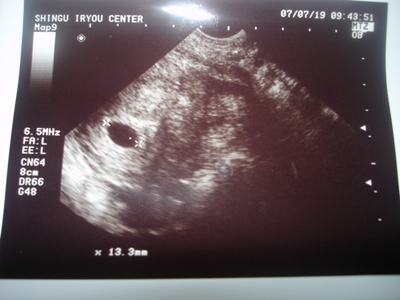

お腹のお豆の赤ちゃん、16㎜に成長してました

心拍も確認でき、元気に心臓も動いてたよ。

ちょうど、お豆ちゃんが動いてる所を見れて、感動です

ななの時は、お豆ちゃんが小さめだったので、生理日数からの予定日より1週遅らされたんだけど、今回は生理日数予定日相当の大きさだそうで、予定日は来年の3/17です。